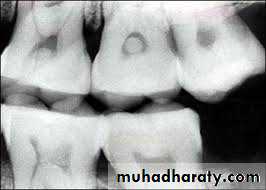

Radiographic Features

• Mostly discovered on routine radiographic examination• The earliest change in the periodontal ligament is found to be thickening of ligament at the root apex

• Lesion may be well circumscribed or poorly defined

• Size may vary from small lesion to large radiolucency exceeding more than 2 cm in diameter.

• Some amount of root resorption has been reported.

Radiographically radicular cyst appears as round, pear or ovoid shaped radiolucency, outlined by a narrow radiopaque margin